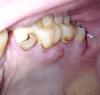

eugene_is Опубликовано 24 апреля, 2011 Поделиться Опубликовано 24 апреля, 2011 (изменено) Не проходит уже несколько недель, иногда перестает ощущаться, иногда кажется, что увеличился в размерах... К врачу как минимум еще пару недель попасть не смогу...Пожалуйста, дайте ответ - что ето и как ето победить в домашних условиях? да, извиняюсь, фото вверх ногами... Изменено 24 апреля, 2011 пользователем eugene_is Ссылка на комментарий

Bier Опубликовано 24 апреля, 2011 Поделиться Опубликовано 24 апреля, 2011 это свищ, надо делать рентген зубов и решать лечить их или удалять.пока можно посоветовать только полоскать рот. Ссылка на комментарий